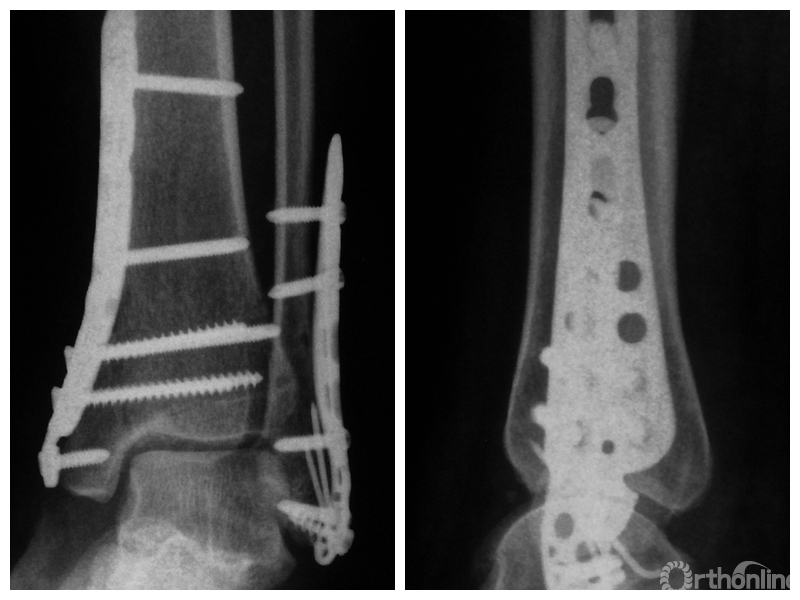

图1 支撑钢板固定组患者,女,63岁,右侧旋后-内收型II度踝关节骨折 a. 术前正侧位X线片;b. 术前CT;c. 术后2周正侧位X线片;d. 术后2年正侧位X线片

图1d 术后2年正侧位X线片

两组患者均获随访,支撑钢板固定组随访时间46~91,平均64.5个月;螺钉固定组随访时间44~86,平均59.5个月。支撑钢板固定组患者术后完全负重时间为(11.5±1.6)周,较螺钉固定组的(12.6±2.3)周显著缩短,比较差异有统计学意义(t=2.05,P=0.04)。X线片复查示,支撑钢板组均获解剖复位,均达愈合;螺钉固定组有20例获解剖复位,2例畸形愈合,1例不愈合,支撑钢板组骨折愈合时间为(11.5±1.6)周,螺钉固定组为(12.0±1.7)周,比较差异无统计学意义(t=1.06,P=0.30)。见图1、2。支撑钢板固定组3例(10%)、螺钉固定组4例(17.4%)发生创伤性关节炎,均采取保守治疗;两组比较差异无统计学意义(P=0.45)。

末次随访时,支撑钢板固定组AOFAS评分为(83.5±9.3)分,其中优8例、良17例、可5例,优良率为83.3%;螺钉固定组AOFAS评分为(76.7±21.2)分,其中优5例、良13例、可2例,差3例,优良率为78.3%。两组AOFAS评分及其优良率比较,差异均无统计学意义(t=1.57,P=0.12;χ2=0.22,P=0.64)。支撑钢板固定组VAS评分为(1.7±1.3)分,螺钉固定组为(2.6±2.1)分,组间比较差异无统计学意义(t=1.92,P=0.06)。随访期间,支撑钢板固定组无手术失败;螺钉固定组3例需行翻修手术,其中1例骨折不愈合合并内固定断裂,2例骨折畸形愈合,手术失败率为13%;但组间比较差异无统计学意义(P=0.08)。